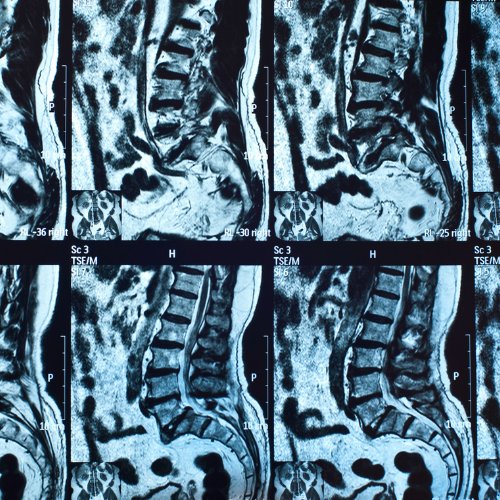

কোমর ব্যথা সার্জারী ( PLID ) সার্জারী